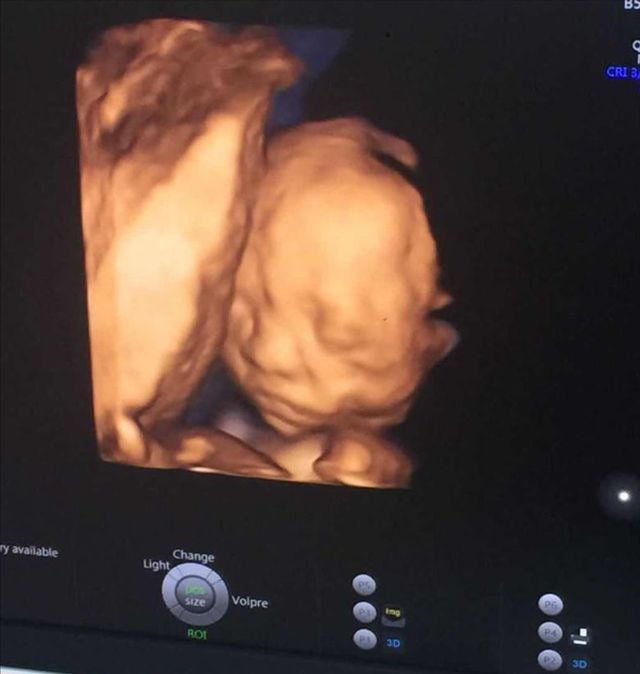

医生:爸爸妈妈可以看向屏幕了

张艺兴:第一次见到动态的汤圆宝宝

张艺兴:乖乖你看到了吗?这是我们的汤圆宝宝

蓝汐我看到了

医生:我这边都检查了一下,其他的都没什么问题,宝宝目前来看应该没什么大碍,等过了48 小时不在有流血的迹象,没什么异常就可以出院了